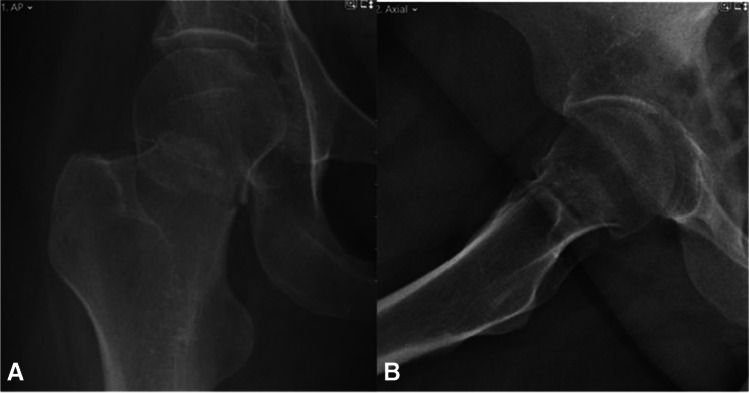

Fig. 4.

A, B AP and lateral radiographs showing intracapsular femur fracture (displaced, Garden 4) of a 39-year-old female. Past medical history consists of cerebral palsy, walks with a cane. Sustained an isolated injury to the right hip after falling from standing height

Fig. 5.

A, B AP and lateral radiographs post-operative day 1, demonstrating fixation of the fracture with FNS

Fig. 6.

A, B AP and lateral radiographs from last follow-up 27 months after surgical treatment. Returned to her preinjury mobility status